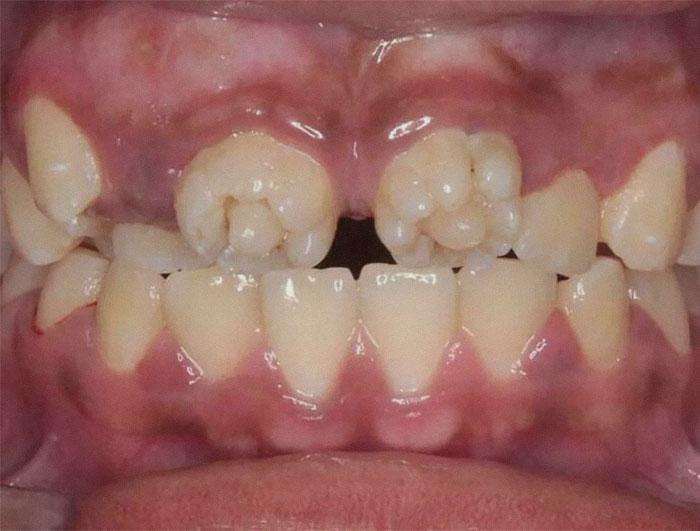

These Are Mulberry Molars, Which Are Associated With Congenital Syphilis

These are Hutchinson's teeth, a sign of congenital syphilis. Mulberry molars are also a sign of congenital syphilis, but these are incisors XD